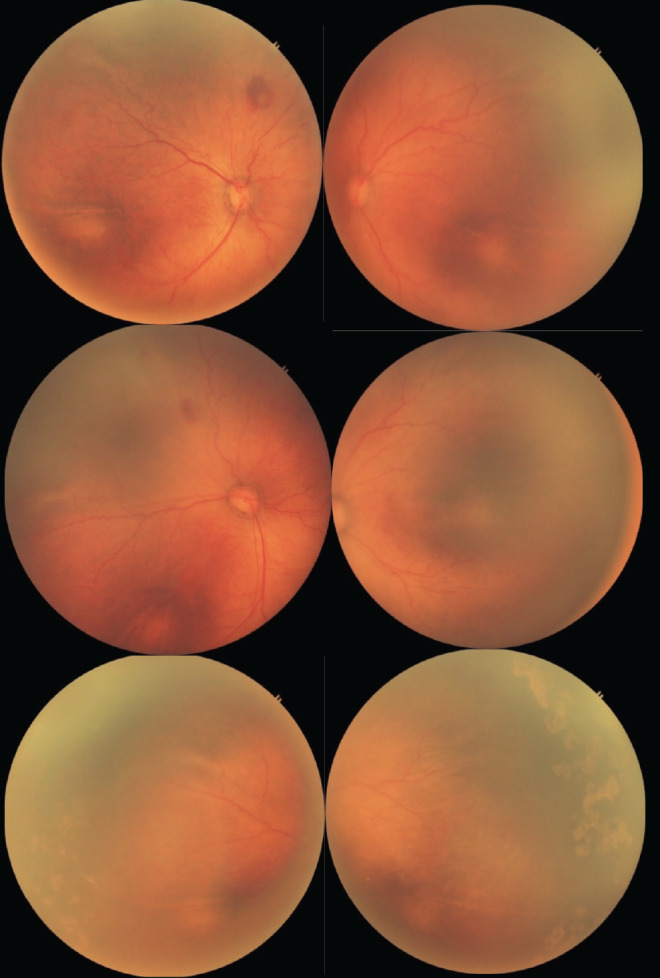

Materials and methods: This study evaluated disease regression and rescue therapy requirement in treatment-naïve ROP cases treated with IVR. Among 188 screened patients, 80 had ROP. Thirty-eight patients (76 eyes) with type 1 ROP and aggressive ROP (AROP) were included. Treatment involved a single dose of 0.2 mg ranibizumab injected under aseptic conditions. Patients were monitored post-treatment for up to 6 months. Recurrence of disease was managed with argon laser photocoagulation targeting the peripheral avascular retina. Data analysis utilized t-tests for continuous variables and χ² tests for categorical data, with a significance threshold of p<0.05.

Results: The study included 19 males and 19 females, with 56 eyes having AROP and 20 eyes with type 1 ROP. All AROP cases required rescue therapy, with a mean interval of 3.43±0.84 weeks between treatments. Sixty percent of type 1 ROP eyes also needed laser therapy. While type 1 ROP cases had slightly higher gestational age and lower birth weight compared to AROP, these differences were not statistically significant (p=0.081 and p=0.27, respectively). However, the interval between treatments was significantly longer in type 1 ROP than in AROP (p=0.0016).

Conclusion: Ranibizumab demonstrated effectiveness in initial disease regression but was linked to reactivation in all AROP and 60% of type 1 ROP cases, highlighting the importance of more frequent follow-ups after ranibizumab injection, particularly for AROP patients.